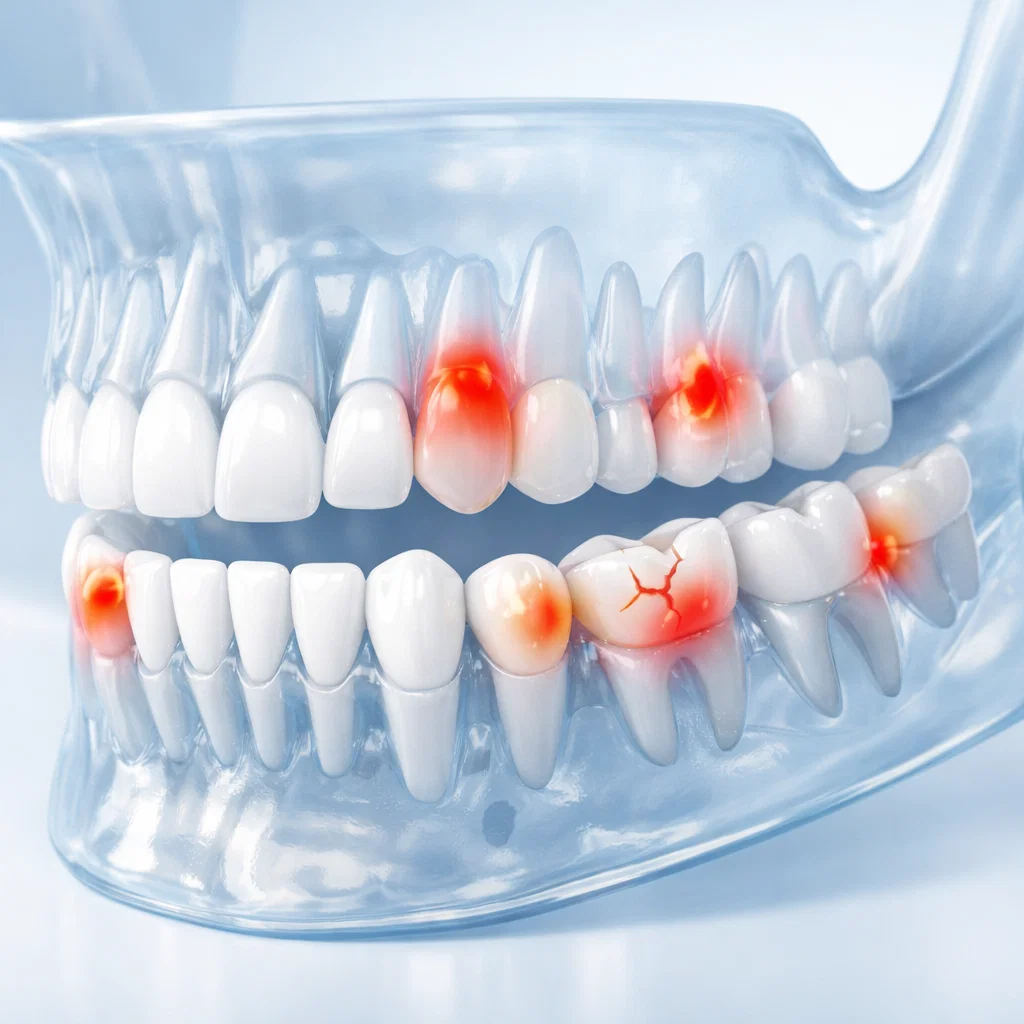

V jakém stavu jsou jednotlivé zuby

Vyšetření ukáže, zda je skus správný a zda jsou dásně zdravé.

Digitální RTG snímky, kontrola dásní a analýzu skusu

Proběhne kontrola zubů, dásní a celkového stavu dutiny ústní.